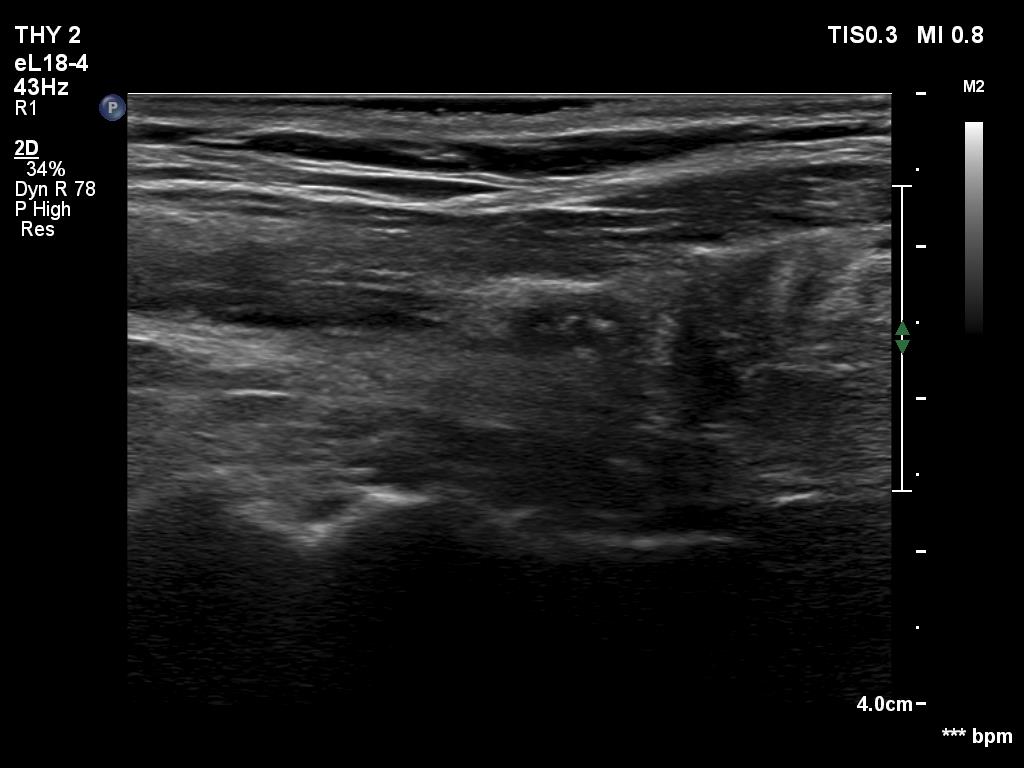

Examination before surgery (first row of images):

Clinical data: A 21-year-old woman requested a second opinion. She has been treated for Graves' hyperthyroidism for three years. The hyperthyroidism relapsed two times. She suffered from mild exophthalmos and occasionally diplopia. Actually, she had no complaints.

Palpation: The thyroid lobes were enlarged. There were no palpable nodules.

Result of blood test: subclinical hyperthyroidism on daily 15 mg methimazole therapy (TSH 0.001 mIU/L, FT4 12.9 pM/L, FT3 4.11 pM/L).

Ultrasonography. The thyroids were echonormal and contained hypoechogenic discrete areas none of them corresponded to a nodule. The echogenicity index was around 30%. The vascularization was average.Surgery was advised. Total thyroidectomy was performed. Histopathology disclosed diffuse goiter, focal lymphocytic thyroiditis.